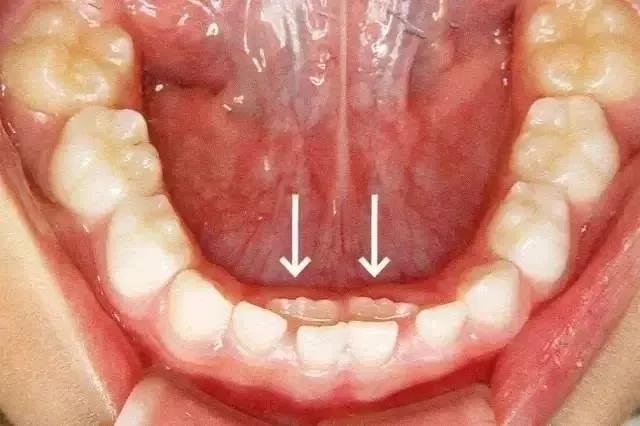

小韩家的孩子刚刚6岁,就已经都很独立了,很久以前开始就可以自己刷牙了,所以她就没怎么操心过孩子牙齿的问题,直到前段时间她的孩子突然哭闹着对她说:“妈妈,我牙齿那里好难受”,小韩经过查看后,这才注意到孩子的门牙那里居然长了两排牙齿,在乳牙还未脱落的情况下,就已经长出了恒牙。

这一发现让小韩难受不已,觉得是自己没有照顾好孩子,最后在医生的诊断下,才知道原来是自己平时给孩子准备的食物太过精细,导致他的牙齿咀嚼不够,没能承担足够的压力,所以导致乳牙没能及时掉落,出现了双排牙现象。医生告诉小韩,只有让孩子多咀嚼硬一点的食物,才能让他们的乳牙自行脱落,否则就只能借用外力来帮助乳牙脱落了,当然也可以用手摇晃孩子的乳牙,加快它们的脱落速度。

首先,最明显的危害就是会导致孩子恒牙长歪,因为如果乳牙不能及时脱落的话,恒牙就没有正常的生长空间了,所以就会形成恒牙、乳牙挤成一堆的情形出现,导致孩子的牙齿无法排列整齐,甚至可能还会因此形成所谓的“地包天”,这对孩子形象的影响无疑是非常大的。